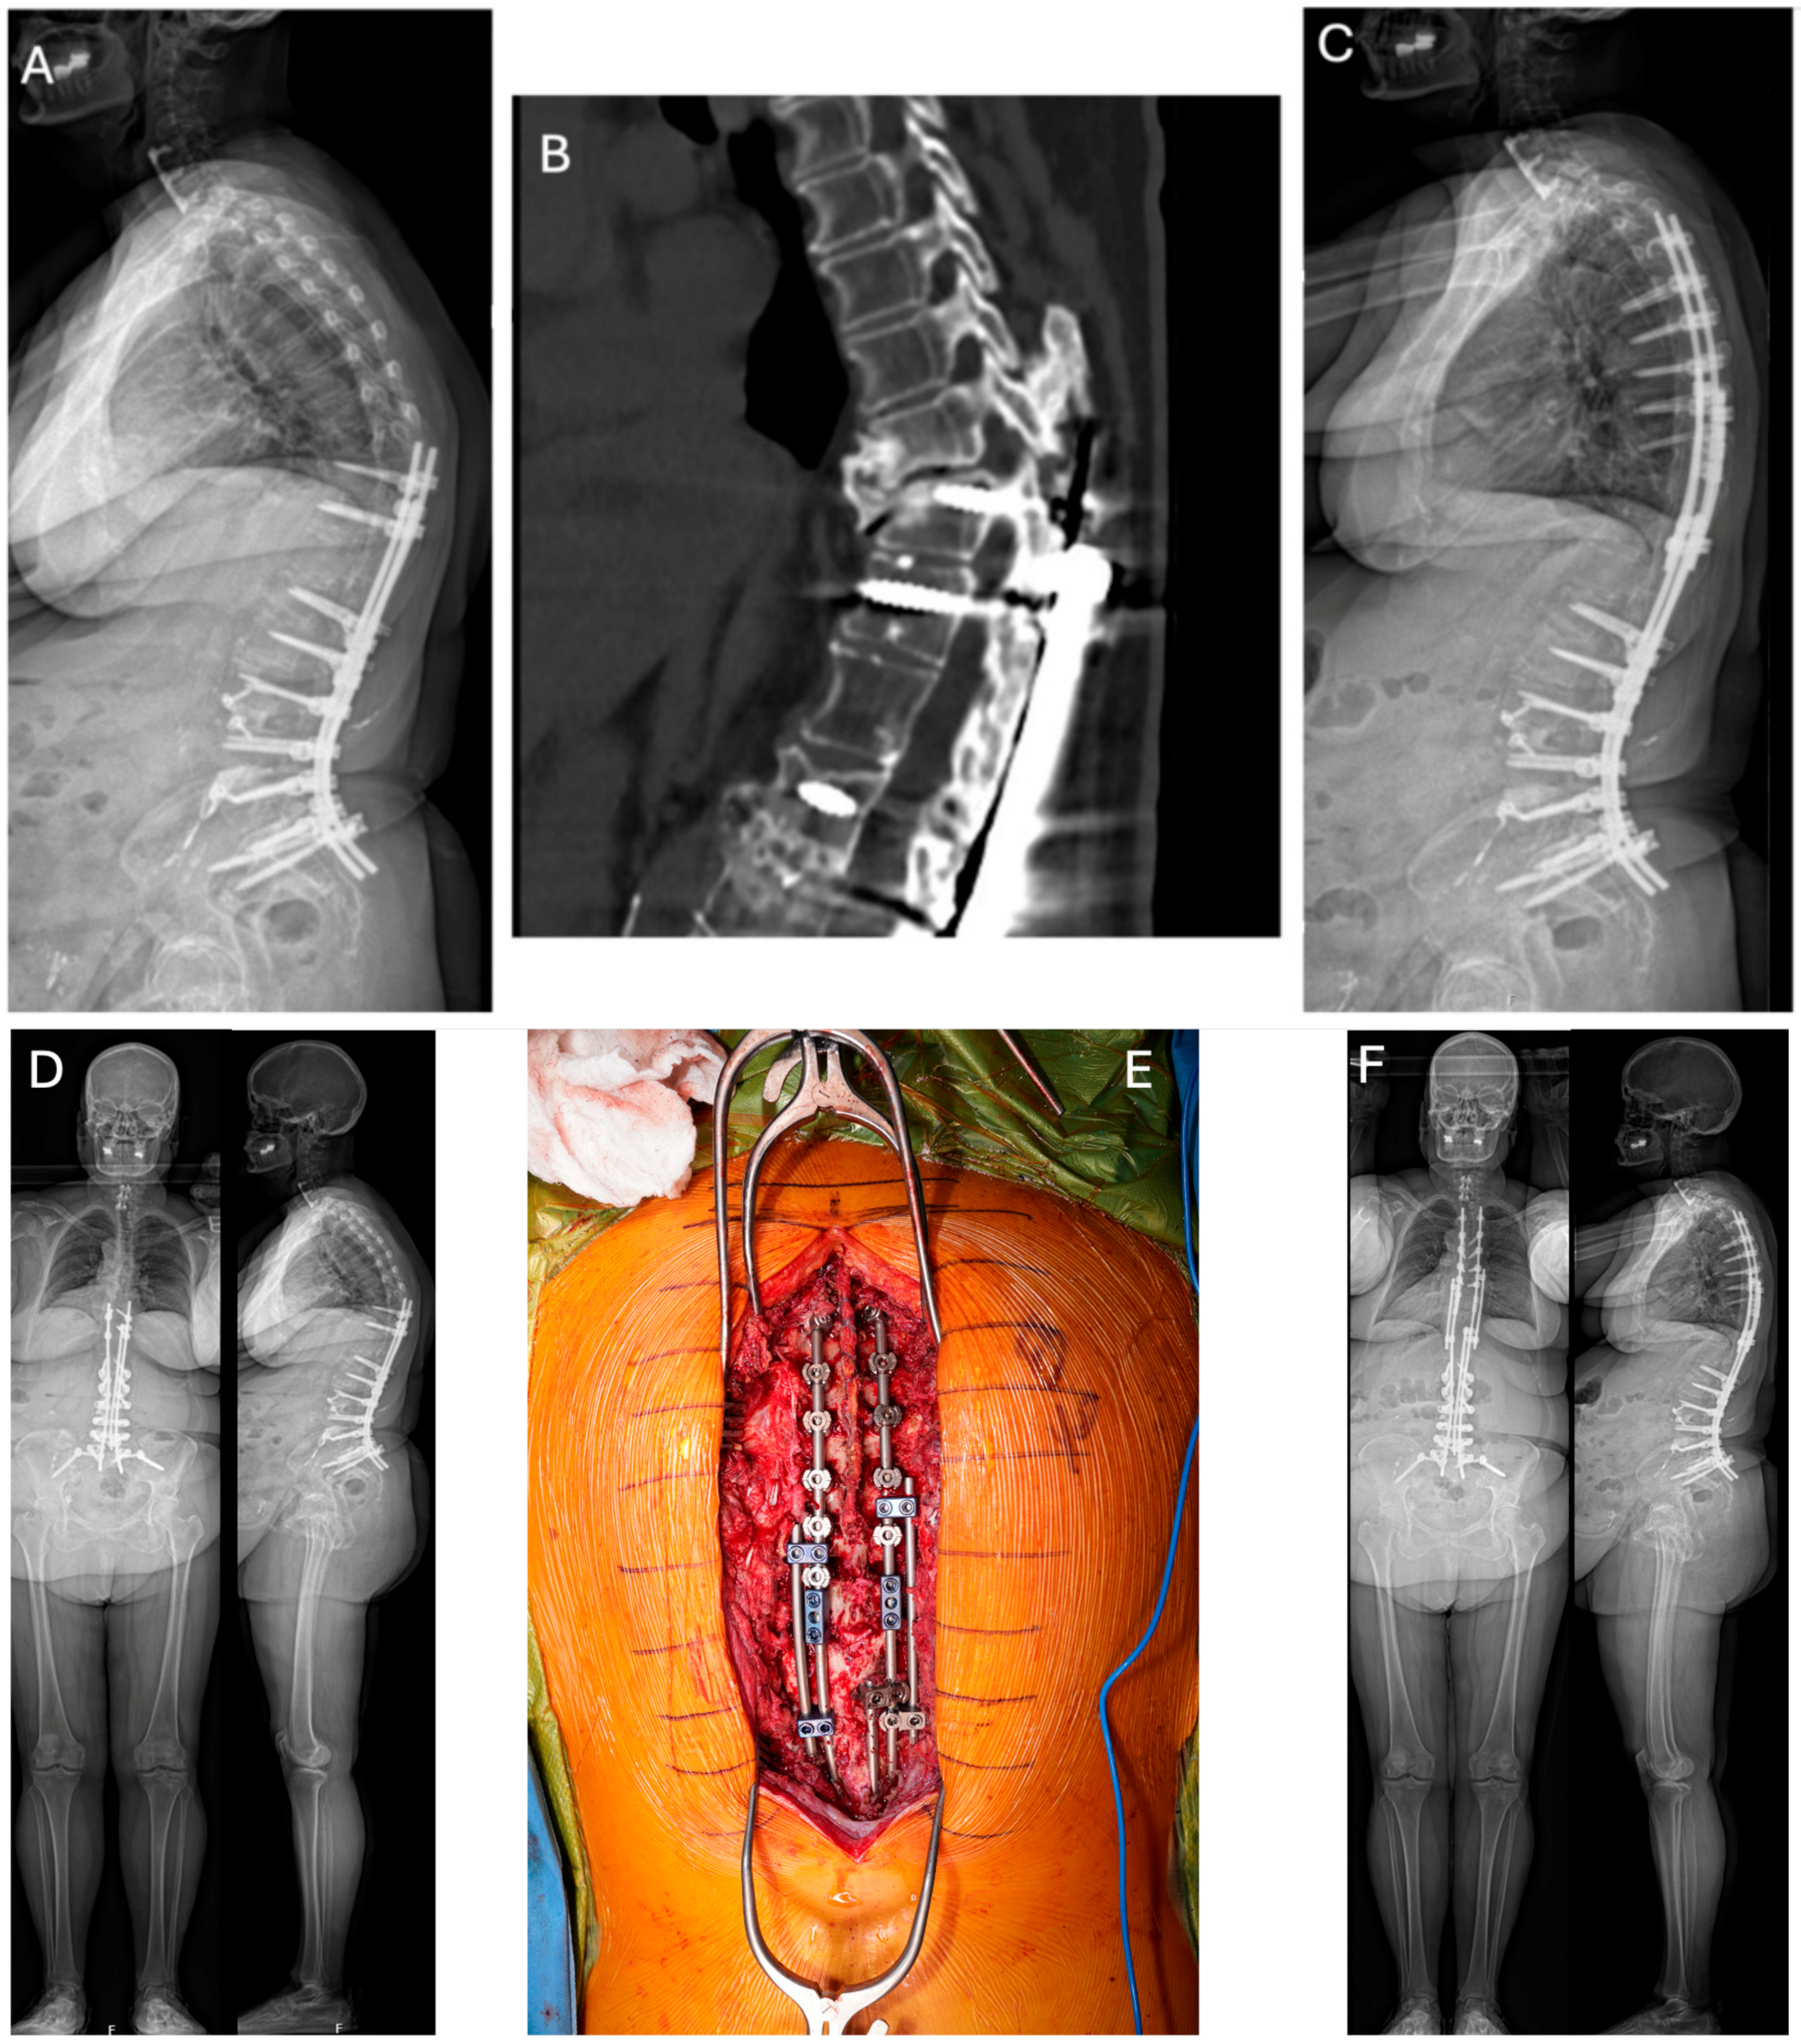

Once the spine is re-exposed, primary instrumentation is typically partially or wholly removed, and the fusion mass is inspected for any defects requiring further bone grafting, decortication, or augmentation with biologic agents such as BMP [66]. Smith-Peterson osteotomies, PSO, or VCR may be performed to correct the focal PJK leading to instrumentation failure (Figure 2A,B), as residual kyphosis poses a significant risk factor for PJK/PJF recurrence [67]. The augmentation of fixation at the UIV to prevent recurrent PJF has also been heavily explored. This has historically involved large diameter UIV pedicle screws of maximum length coupled with polymethylmethacrylate (PMMA) cement augmentation to decrease screw pullout and the risk of construct failure [68,69]. Sublaminar tethering to augment the posterior ligamentous tension band cranially in the revision setting has also been explored but is primarily a prevention strategy [70]. A combination of medical optimization and thoughtful surgical technique are critical to achieving a successful result when treating PJK/PJF.

Figure 2.

Lateral 36″ radiographs (A,C) and sagittal CT reconstruction (B) of a 58 year-old female with history of combined L1–L5 anterior lumbar interbody fusion and T10-Pelvis posterior spinal fusion, complicated by infection requiring irrigation and drainage, who presented 1 year post-operatively with proximal junctional kyphosis (A,B). She underwent removal of instrumentation, revision posterior spinal fusion from T4 to T11 with Smith-Peterson osteotomy at T9-T10 (C). (D) Pre-operative EOS PA and lateral radiographs demonstrating proximal junctional kyphosis with global sagittal imbalance in the same patient shown in (A,B). (E) (top = cranial; bottom = caudal): Intra-operative clinical photo demonstrating the final construct used to address the proximal junctional failure and restore the sagittal plane following Smith-Peterson osteotomy at T9–T10. End-to-end connectors were utilized to connect the rods placed in the new instrumentation from T4 to T9 with the previously placed instrumentation. Side-to-side connectors were also placed at T8–9 on the left and T7–8 on the right and connected at T12 on both sides. (F) Post-operative EOS PA and lateral radiographs highlighting improved global alignment following removal of instrumentation, revision posterior spinal fusion from T4 to T11 with Smith-Peterson osteotomy at T9–T10.